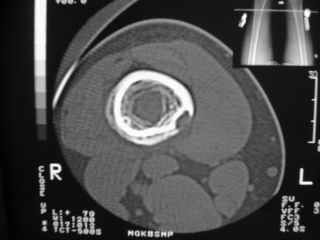

Здравствуйте, уважаемые коллеги!Представляю вашему вниманию интересный случай и пока что непонятный для меня в диагностическом плане. На днях в наше отделение (детской ортопедии и травматологии) поступил 13-летний мальчик по направлению из поликлиники с диагнозом: остеома нижней трети правого бедра.

Анамнез практически никакой: в следствие травмы (растяжение связок коленного сустава) от 07.11.2004 выполнены Rg-граммы в травмпункте и обнаружено опухолевидное образование. Первичные Rg-граммы я не публикую, так как они заметно худшего качества, да и динамики за прошедшие три недели не отражают. Болевой синдром купирован в течение трёх дней. В настоящий момент мальчика ничего не беспокоит. Ходьба не нарушена, опухоль пальпируется с трудом по задней поверхности в н\3 правого бедра, пальпация безболезненна, объем движений в суставах правой нижней конечности полный и симметричный. Кожа над опухолью не изменена.В нашей клинике проведено дополнительное обследование: общие анализы крови и мочи, биохимия крови без особенностей. Выполнены Rg-граммы на цифровом Siemens обычные и продольные томограммы срезами 3-5 мм, а также компьютерная томография поперечными срезами по 5 мм. Прошу обратить внимание, что на приведённых томограммах видны две полости 10х15 мм и 15х60 мм. Также имеются два опухолевидных образований наслаивающихся друг на друга: уплощённое и вытянутое 10х100 мм и элипсовидной формы 15х30 мм. Это хорошо заметно на фото a_1.jpg c_1.jpg и d_1.jpg. Плотность внутри полостей 125% от плотности костномозгового канала, плотность наружного опухолевидного образования 55% от плотности кортикального слоя. Также отмечается линия перелома по центру наружного опухолевидного образования.Исходя из полученных данных мнения в плане диагноза несколько разделились от 1)сочетания кортикальной фиброзной дисплазии и латентно протекавшего маршевого перелома н\3 правого бедра до 2)остеосаркомы. В отношении первого варианта не сходится отсутствие клиники при переломе такой крупной кости как бедро, второй вариант вообще оставлю без комментария, ибо некомпетентен. Хотелось бы услышать мнения коллег, с удовольствием ознакомлюсь с любыми предположениями и замечаниями.С уважением, Александр Е. КлоковОтделение детской ортопедии и травматологииБСМП г. Мурманска.

Структура области опухолевидного образования больше всего напоминала перестройку характерную для костной мозоли, никаких визуально инородных структур не выявлено.

С облегчением спешу сообщить, что гистологический анализ подтвердил сложившееся интраоперационно мнение, что мы имеем дело с посттравматической перестройкой костной ткани (костной мозолью). Плюс к этому фиброзные кортикальные дефекты. В обшем, зла нет и слава Богу.